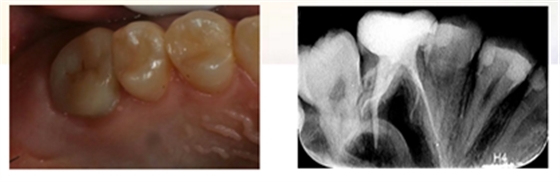

检查:26冠部大面积龋损,仅余近中颊侧残壁,残余牙体颜色变暗,牙龈增生至缺损牙体组织内部,髓腔内炎性牙髓组织增生呈息肉状。探诊(+),冷诊(±),叩诊(-),无松动。

X-ray示:26远中低密度影已穿通髓腔,与近中低密度影几近相连。根尖无低密度影像。

诊断:26慢性牙髓炎